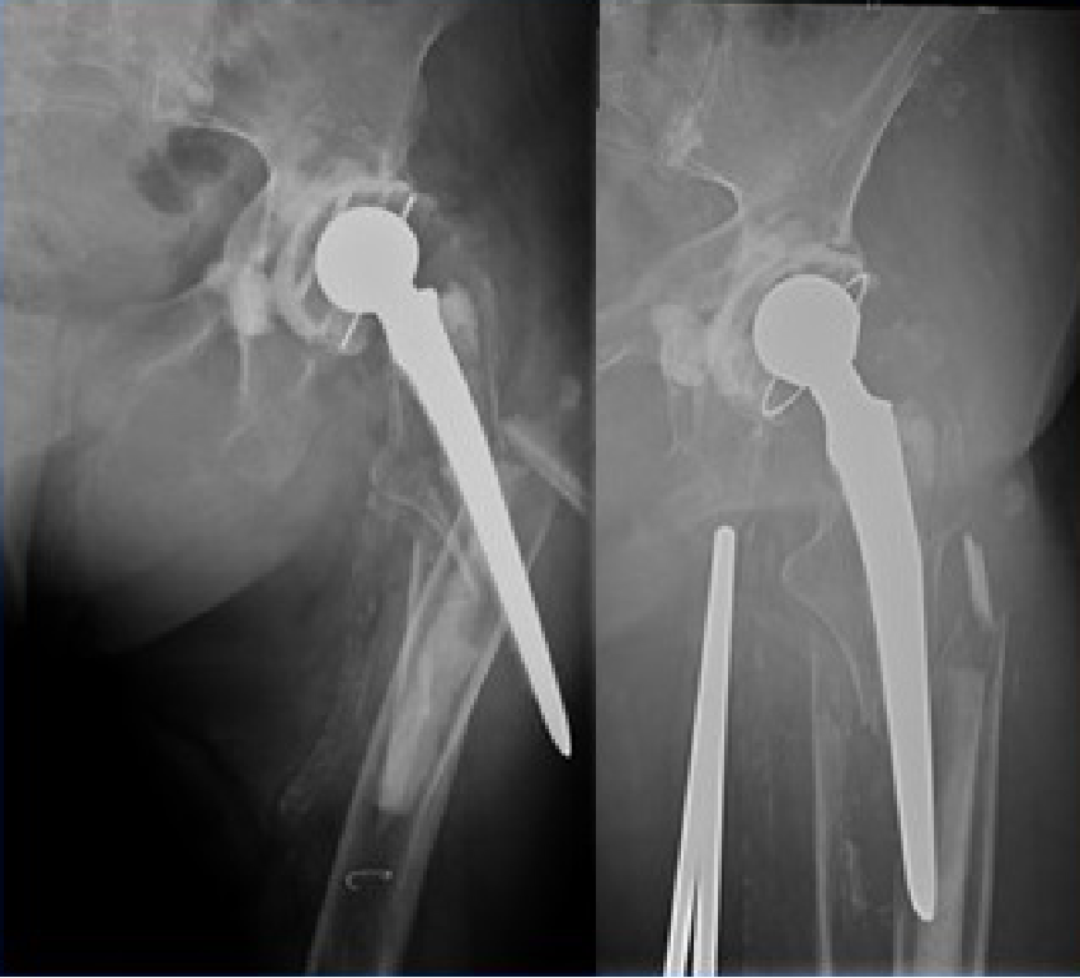

6. 假体周围骨折:

发病率 1%~2%。可发生在书中或术后。迟发性骨折多发生于股骨假体尖端。非骨水泥假体植入和翻修术更容易发生术中骨折。

Ag 型(累及大粗隆)

Al 型(累及小粗隆)

B1 型假体柄固定牢固

B3 型假体柄松动且伴骨质疏松

C 型骨折位于股骨假体尖端远处,假体稳定。